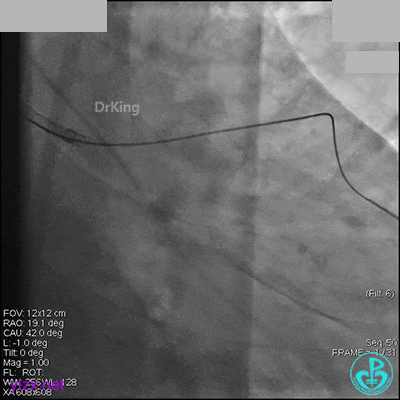

1周后再次上台,右冠脉3级血流,3段局限性严重狭窄,内膜模糊,应该是上次操作夹层遗留下的血肿。

先处理前降支开口严重狭窄并顺利植入前降支到左主干支架。